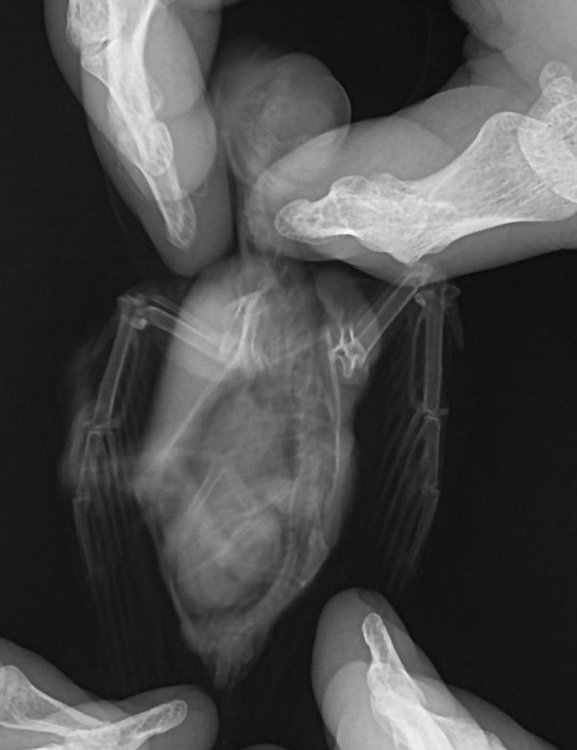

Добрый день. Три дня назад подобрал на улице птицу с неестественным положением правого крыла (о том, что это стриж узнал от ветеринарного врача). Занес в ближайшую ветеринарную клинику, где врач, осмотрев и ощупав птицу (рентгена в клинике не было), сказал, что перелома нет, скорее всего стриж ударился о провод и ему необходимо несколько дней для восстановления. Никогда не имел дел не только со стрижами, но и с птицами вообще, но решил попробовать его спасти. Живет в коробке примерно 30х30х30, кормлю опарышами, так как пока не нашел других насекомых, этот вопрос решу в ближайшее время. Вопрос с питанием отдельная проблема. Больше всего меня беспокоит его крыло. Сегодня свозил птичку на рентген. Врач хотя и увидел перелом, но о лечении птиц знает примерно столько же сколько и я. Даже не знал, как называется сломанная кость (называл её маленькой) Я потом посмотрел в интернете, что это лучевая кость. А локтевую кость называл маховой. Предложил зафиксировать крыло и, прижав крылья к телу, замотал его эластичным бинтом. Приехав домой, я снял эту повязку. Не знаю смогу ли найти ветеринара по птицам, а пока прошу совета и помощи у знающих людей. Есть ли шанс вылечить птицу с таким переломом? Нужно ли её пеленать, как сделал этот врач? Может быть поместить стрижа в маленькую коробочку, чтобы у него не было возможности махать сломанным крылом? В общем, что сейчас делать с птичкой? Спасибо за советы PS На последнем снимке стрижик завернут в эластичный бинт